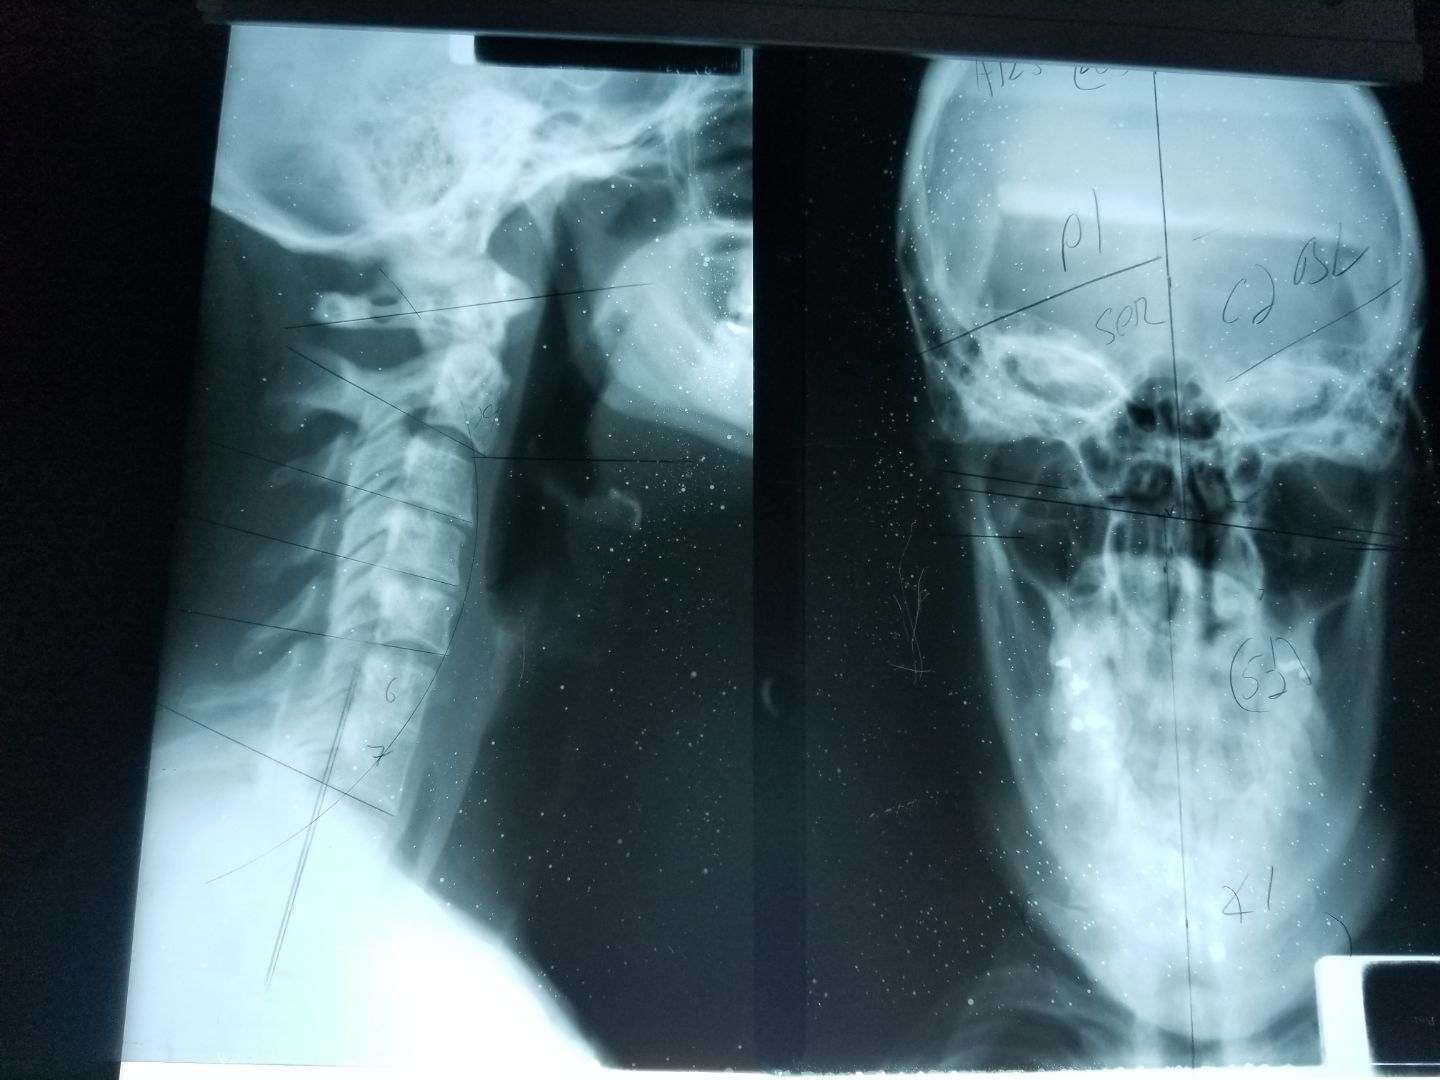

This past week Crystal, our oldest, went to a new Chiropractor as she continues to have issues with her back and neck. She has seen a wide variety of Chiro's, Massage Therapists, and even an Empath. All to no long term satisfaction. This time X-rays were taken.

NOT good.

We are all hopeful that this new guy will be able to make a difference. Of course he thinks he can.